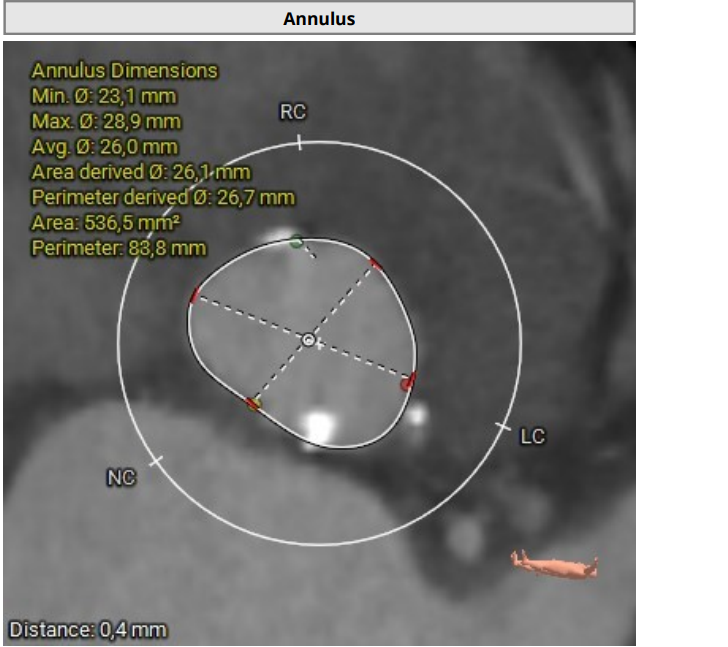

Since 2023 - frequent hospitalizations due to attacks of chest pain, attacks of nocturnal asthma. According to echocardiography - EF-52%. AV leaflet opening 0.5 cm. Prominent calcification of the aortic valve and fibrous ring. V-5.9 m/s, PGmax-140 mmHg, PGmean-88 mmHg, S-0,5 cm2. Aortic regurgitation grade II. Mitral regurgitation grade II-III. No zones of local contractility disturbance. Consulted with a cardiac surgeon, surgical correction of aortic defect was recommended.

The rightsubclavian vein was punctured. A 6F intraducer was inserted. The endocardialelectrode for temporary cardiac stimulation was placed in the right ventricularcavity. The left radial artery was punctured. A 6F intraducer was placed, andan invasive pressure line was connected. The left common femoral artery waspunctured. The 6F intraducer is inserted. Pigtail 6 F diagnostic catheter isinserted into the non-coronary sinus. Puncture of the right common femoralartery was performed. Two intravascular sutures were placed using the Pro Glidepre-stitching technique. The 12F intraducer was placed in the lumen of the rightfemoral artery. The Confida wire wasguided into the left ventricular cavity. Aortic valve valvuloplasty wasperformed using balloon catheters 20.0-40.0 mm, 25.0-40.0 mm. Asystole wasregistered on ECG and resuscitative measures were started. During indirectheart massage, endovascular prosthesis Portico - 29mm was implanted in aorticposition. At the control aortography, the aortic valve prosthesis is optimallyspread out.